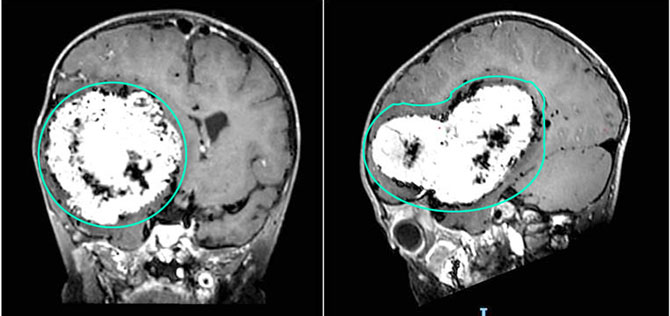

近日,我院收治了一名“发作性意识不清”只有两岁的小朋友。见到患儿时,表现为精神萎靡、行走不稳,并伴有左侧肢体活动减少,家长描述其近期反应明显迟钝,与同龄儿童相比行为异常,还反复呕吐。这些症状引起了医生的高度警惕,马入收治入院。经头部MR增强检查,发现右侧大脑半球存在一巨大颅内占位,肿瘤直径约10厘米,严重压迫周围正常脑组织,病情十分危急。为了挽救这位小患者的生命,广东省人民医院周东主任团队立即决定实施手术,以期彻底切除肿瘤。

术前影像资料可见右侧大脑半球巨大肿瘤占位